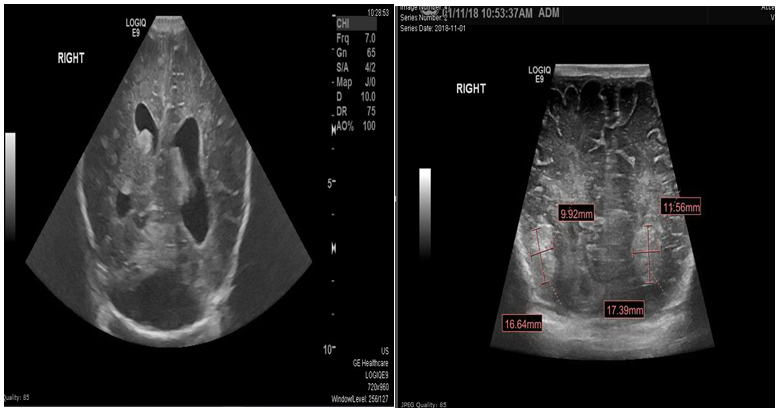

The initial examination showed small for age newborn, his growth parameters were all below 3rd centile donating intrauterine growth restriction. Grossly dysmorphic with wrinkled skin, flexed posture, abnormal head shape, high forehead, depressed nasal bridge anteverted nostrils, low set ears, micrognathia, proptosis, thick eyelashes and eyelids, partial syndactyly of 2nd and 3rd toes bilaterally with flattened feet and hands. The abdomen was bulging with palpable hard left upper quadrant mass, about 4cm, liver edge also felt below costal margin. The newborn was connected to mechanical ventilation for one day, extubated to CPAP, weaned to nasal cannula for another 3 days then he was off respiratory support till discharge. First x ray showed homogeneous soft tissue opacity occupying the left abdominal cavity pushing the bowel loops to the right side most likely the left enlarged kidney(Figure 1). Ultrasound scan revealed average size of both hepatic lobes with smooth surfaces, coarse hepatic parenchymal texture with diffuse periportal thickening, and extensive thick GB sludge. The Left Kidney was hugely enlarged Multicystic dysplastic with multiple sizable cortical cysts. It measures 6.7x3.8cm; right kidney was normal (Figure 2).

Figure 1 Chest and abdomen X ray showing homogeneous soft tissue opacity is occupying the left abdominal cavity pushing the bowel loops to the right side.